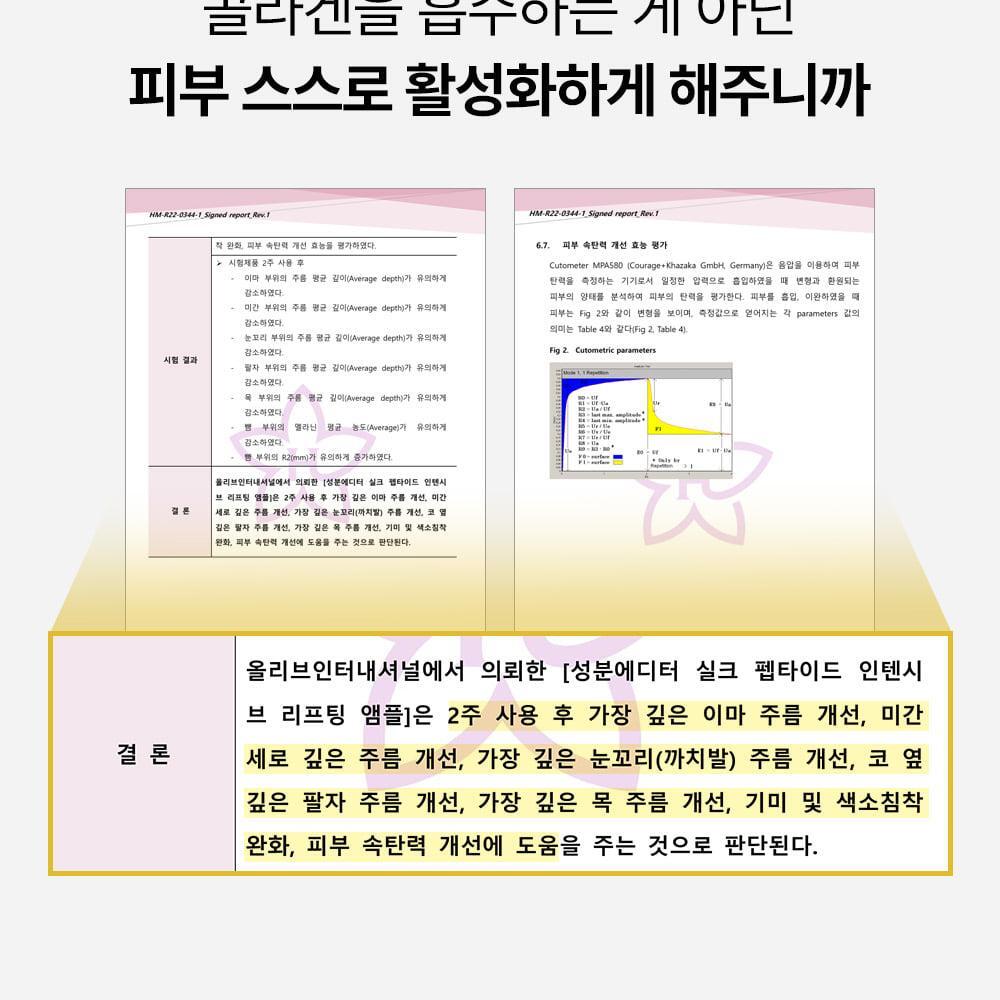

- 已完成人體應用測試。單次使用即可感到提拉緊緻效果。而且這不是暫時的效果。 24小時持續提升力量。持續用更見效果。

成效數據

額部皺紋起始處提升率:83.57%

臉頰深層脂肪突出處提升率:82.11%

嘴角凹陷處提升率:56.73%

下巴皮膚皺摺處提升率:51.64%

眼周易生皺紋處提升率:47.37%

- 即時效果──「2週持續使用」看得見的改變。